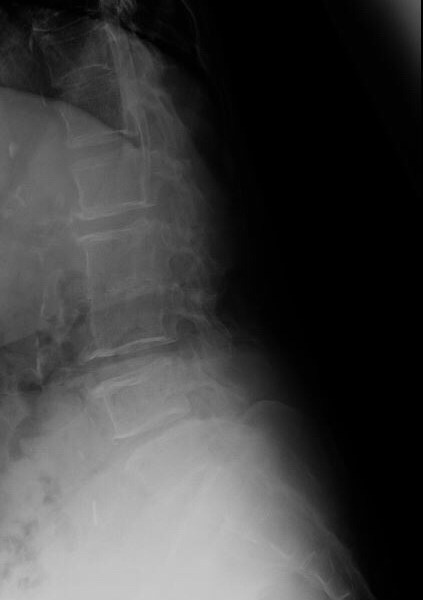

An X-ray of the lumbosacral spine showed narrowing of the L2-L3 disc space following which an MRI of the spine was arranged. Blood cultures were positive for Streptococcus bovis.

The MRI showed degenerative changes at L2-L3, but more importantly, spondylodiscitis at S1-S2, with impingement of nerve roots (which would explain the symptom of buttock pain. This is most plausibly attributed to the Streptococcus bovis bacteremia.